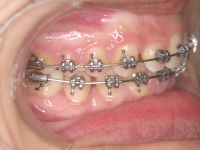

Premolar mandibular incluido + fenestración

45 incluido